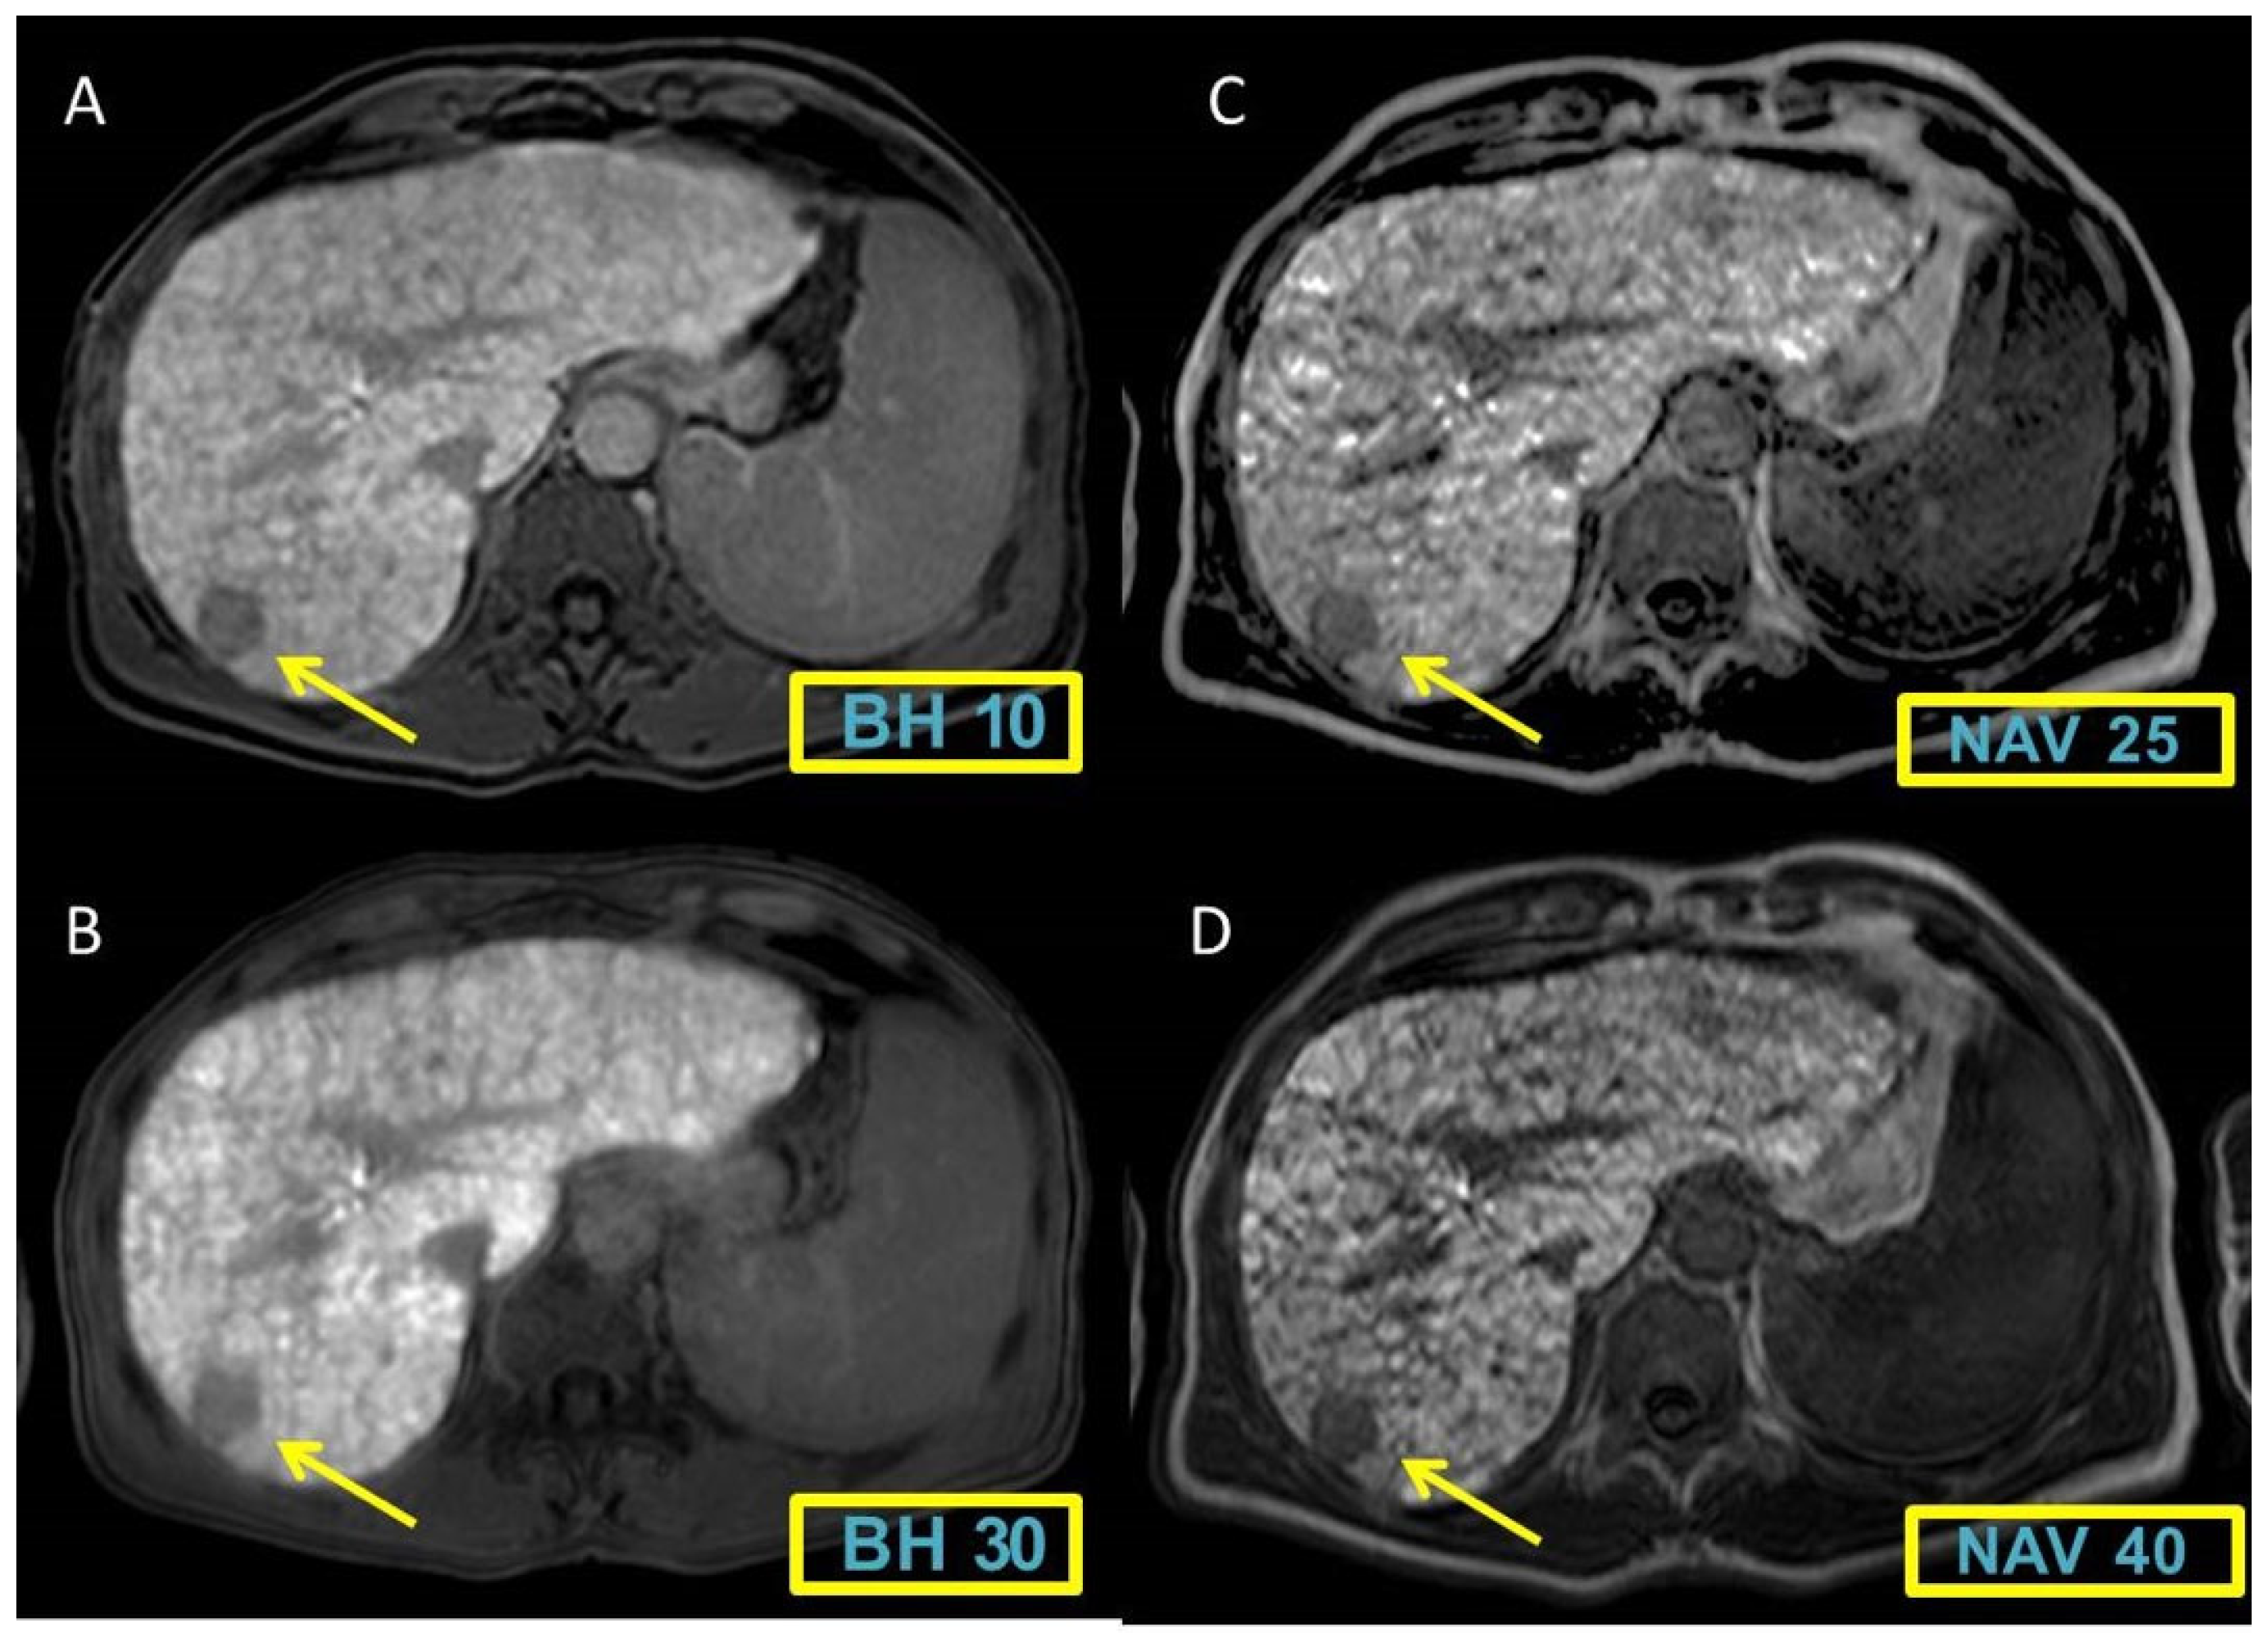

Figure 1 and Figure 2 display representative cases to visually illustrate these findings, providing a clear view of how different MRI sequences affect the CNR between liver and spleen tissues.

Figure 1. Breath-hold (BH) sequences (flip angle 10° and 30°) (A-B) and free-breathing navigated sequences (NAV) with flip angle of 25° and 40° (C-D). Free-breathing navigated sequences show a better enhancement with a higher image contrast compared to Breath-hold (BH) sequences.